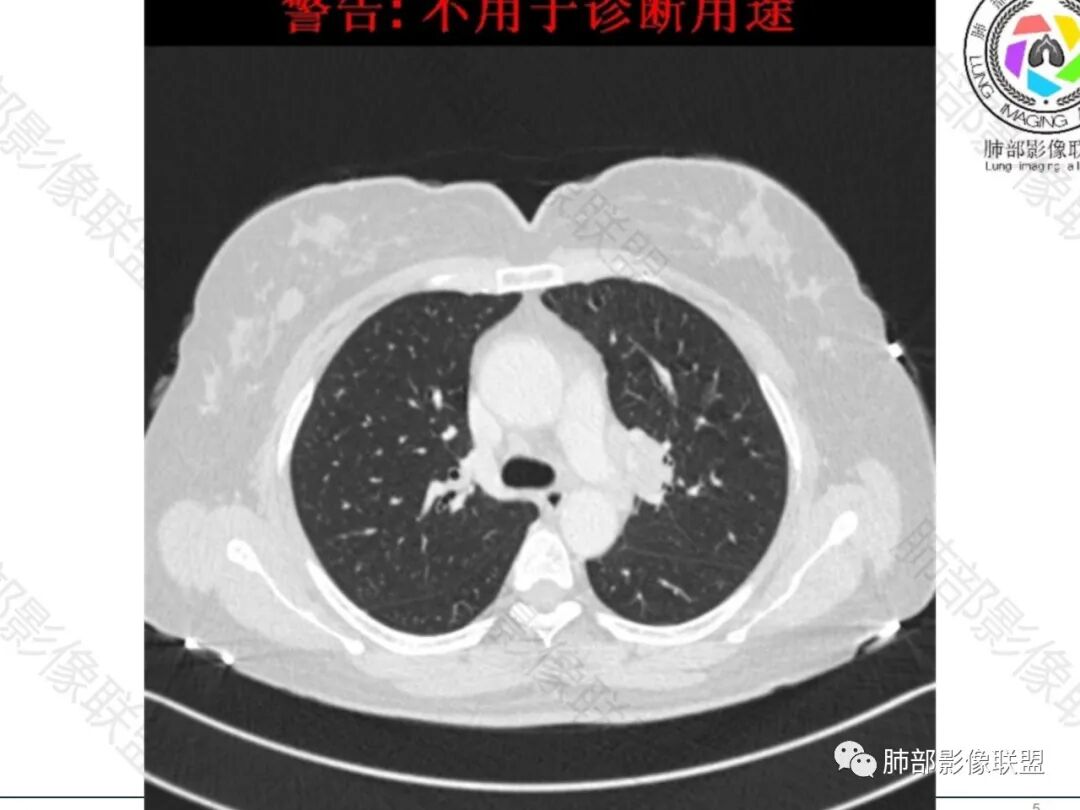

左肺门增大,可见一实性结节,病变跨叶裂生长,边缘平直,膨隆,平扫密度均匀,增强后可见均匀强化,病变包绕血管束,血管走行自然,纵隔淋巴结肿大,右乳腺似有一小结节?临床:女性47岁,无感染症状,考虑:淋巴瘤,小细胞肺癌,结核(坏死不明显),结节病(单侧少见)

中年女性患者,轻咳月余,胸部CT:左肺门肿块,边缘光滑,内部密度均匀,包绕支气管及肺动脉。纵隔淋巴结增多,部分增大。考虑恶性SCLC可能。

左肺门占位,包绕支气管血管,支气管狭窄未见堵塞,考虑淋巴瘤

中年女性患者。左肺门上区, 围绕左肺动脉及支气管旁不规则形的病灶,支气管无变窄,肿块塑形增长,密度均匀,增强后边界比较清楚,肿块未见强化。临床提供给的病史价值不高,表现为轻咳,偶感乏力。影像学表现出偏温和的特点。考虑淋巴瘤。

中年女性,临床症状不明显,左肺门肿块影,边缘清晰,可见分叶,包绕支气管生长,右侧肺门可见增大淋巴结,增强病灶强化不明显,可见血管漂浮征,考虑肿瘤性病变,淋巴瘤,小细胞癌,神经内分泌癌。

女性,47岁,轻咳月余。CT示:左肺门不规则病灶,包绕气管血管生长,增强扫描轻度强化,纵隔可见略大淋巴结,临近支气管受压狭窄。综合考虑为恶性,淋巴瘤或小细胞肺癌可能

左肺门肿块,边界清晰,跨叶间裂生长,病灶整体感觉偏软,包绕血管及支气管,增强后轻度均匀强化,无坏死,考虑淋巴瘤可能大

流心明智:

女,47,轻咳月余,偶感乏力。胸部CT:左肺门肿块,跨叶裂,边缘膨隆,平扫密度均匀,增强后可见均匀强化,病变包绕血管,血管走行自然,纵隔多发淋巴结肿大(2R、3A、4R、4L、5、6、L10-13),右乳腺有一小结节。考虑:淋巴瘤>小细胞>转移>TB>结节病。

左肺门为主,纵隔有一些,多发,融合成团,密度均匀,强化均匀,边界比较清楚

血管包绕其中,明显侵犯不典型

应该是小叶间隔增厚了

似乎还有结节

但是小叶间隔增厚了,提示间质来源为主病变